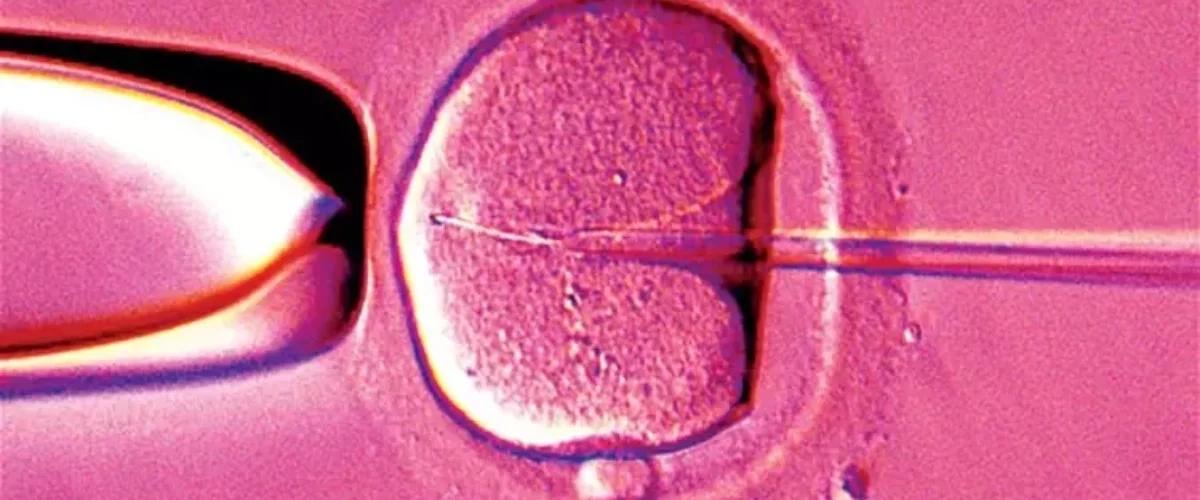

Между тем впереди еще длительный этап наблюдений за детьми. Дело в том, что при переносе ядра оплодотворенной яйцеклетки в донорскую яйцеклетку, очищенную от ядерной ДНК, часть патогенных митохондрий может переноситься вместе с ядром. По мере развития эмбриона доля патогенных митохондрий может увеличиваться до того уровня, чтобы вызвать заболевание.

У трех детей ученые обнаружили от 5% до 16% патогенных митохондрий от общего числа. «Это очень низкий процент, но он все равно выше, чем мы ожидали», — заявили они. В дальнейшем будет важно изучить не только кровь и мочу, но и другой биоматериал детей, поскольку уровень патогенных митохондрий может варьироваться в разных тканях и меняться со временем.